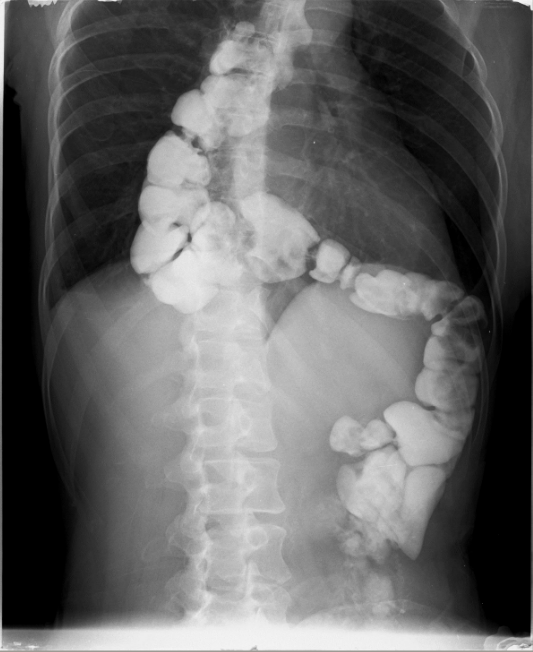

Extreme stenosis of the involved transverse colon . Residual seeds were unable to overcome the stenotic segment (Courtesy Dr. V. Penopoulos)